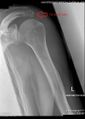

التباين

هناك ثلاثة أنواع متميزة من ناحية التشكّل (المورفولوجية) للأخرم ، ووجود علاقة ارتباط متلازم بين هذه الأشكال وتمزق عضلة الكفة المدورة:[2]

النوع الانتشار زاوية الميل

الوحشي

تمزق

عضلة الكفة المدورة

مفلطح 17.1% 13.18 3.0%

مقوّس 42.9% 29.98 24.2%

خطاّفي 39.3% 26.98 69.8%